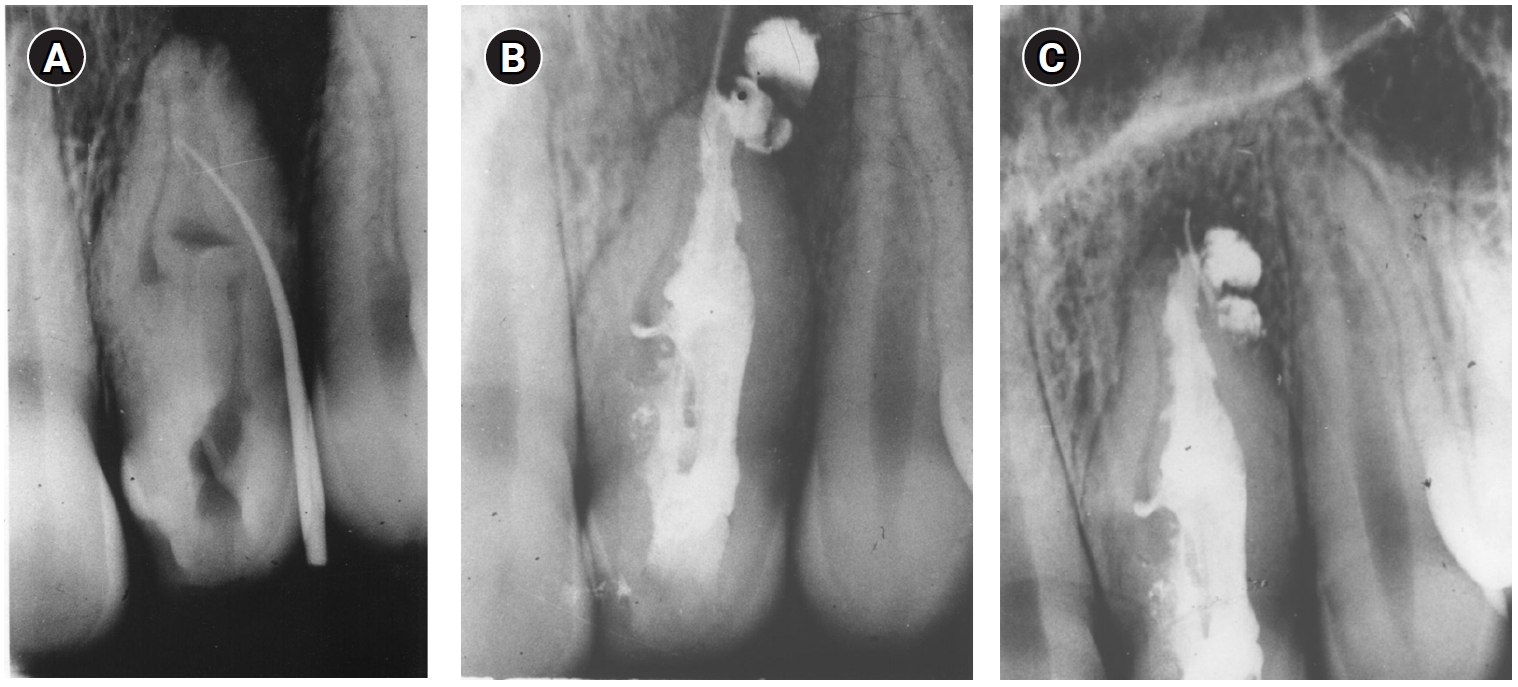

Thirty years later (2002), the patient came back to the department with a complaint of pain and swelling and was diagnosed with an acute apical abscess in tooth #22. Informed consent was obtained and endodontic surgery was performed in the department (Figure 2). The tooth was treated with a modern surgical endodontic protocol, involving a dental operating microscope: local anesthesia with lidocaine 2% with epinephrine 1:100,000, triangular full mucoperiosteal flap, osteotomy, root-end resection with no bevel using a high-speed bur, curettage, retrograde preparation using ultrasonic tips, and root-end filling with intermediate restorative material (IRM; L.D. Caulk Company, Milford, DE, USA).

Clinical and radiographic follow-up was scheduled annually. Radiographic outcomes were assessed based on the criteria established by Rud et al. [17]. At a 2-year follow-up, the tooth was clinically asymptomatic, with good adaptation of the crown to the tooth and with radiographically normal periapical tissue (Figure 2C). The tooth remained asymptomatic with radiographically complete healing at an additional follow-up visit in 2006 (Figure 2D).

Endodontic surgery on tooth #22. (A) Preoperative radiograph in 2002 showing periapical radiolucent area around the apex and distal aspect of the root. Note the excess filling material outside the root. At the time of referral, the tooth had been restored with a post and crown. Marginal defects can be seen in the final restoration. (B) Intraoperative photograph in 2002. (C) Postoperative radiograph in 2002. The apical part of the mesial cavity was prepared and filled. Excess filling material that was outside the root was removed. (D) Four-year follow-up radiograph in 2006 showing complete healing with no periapical radiolucency present.

Figure 2. Endodontic surgery on tooth #22. (A) Preoperative radiograph in 2002 showing periapical radiolucent area around the apex and distal aspect of the root. Note the excess filling material outside the root. At the time of referral, the tooth had been restored with a post and crown. Marginal defects can be seen in the final restoration. (B) Intraoperative photograph in 2002. (C) Postoperative radiograph in 2002. The apical part of the mesial cavity was prepared and filled. Excess filling material that was outside the root was removed. (D) Four-year follow-up radiograph in 2006 showing complete healing with no periapical radiolucency present.